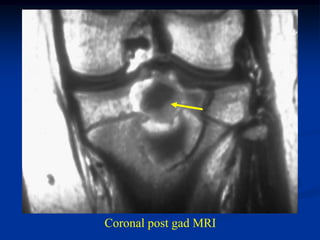

CLASSIC Case #123

12 year female with chondroblastoma proximal tibia

Coronal post gad MRI

Sagittal T-2 MRI